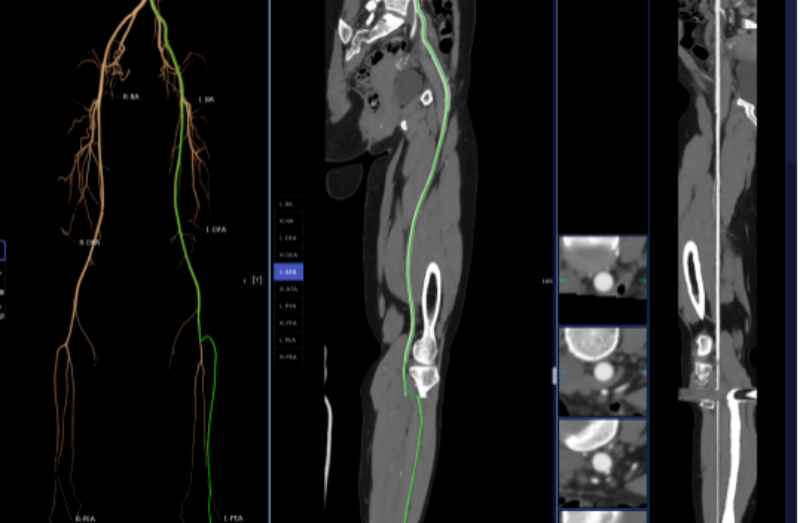

血管诊断、脑血管灌注成像

头颈部CTA、冠状动脉CTA、肺动脉CTA及肢体CTA是一种无创、低风险、快速的检查方法,能够清晰识别血管狭窄、畸形或斑块,明确病灶与周围正常组织的位置关系,为治疗方案的制定提供有力依据,能提高患者生存率,缩短高危患者急救救治时间。

以往,放射科医生进行头颈部CTA和冠状动脉CTA重建后处理,需要医生应用工作站手动处理,耗时约20-30分钟。而AI人工智能辅助诊断系统通过计算机视觉和深度学习技术,仅需5-10分钟即可完成影像重建的后处理计算,一键生成精准的三维重建图;系统还能自动标记血管名称、快速判断斑块性质,并根据最新指南对狭窄程度进行分级诊断等,帮助医生快速定位病变节段,准确分析斑块类型及狭窄程度;对脑血管灌注成像进行快速重建和诊断,大幅缩短患者等候检查和获取诊断报告的时间。